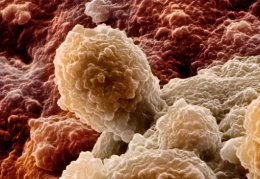

Ученые, копаясь в костях доисторической рептилии, нашли новую информацию о раке, которая возможно поможет им в будущем с лечением от него. Открытие произошло в Вашингтонском университете в Сиэтле.Сообщается, что при осмотре черепа вымершего животного, в нем обнаружили опухоль, развивающуюся при нарушении системы зубов. Как сообщается, такие опухоли являются частыми среди современных животных. Этот факт дает пересмотреть некоторую информацию об опухоли. Например то, что опухоли начали развиваться не раньше появления современных млекопитающих.

Автор открытия заявляет, что до этого момента у млекопитающих возрастом более миллиона лет не удавалось обнаруживать подобное. Благодаря этому можно предположить, что опухоли были и раньше, чем появились современные млекопитающие.